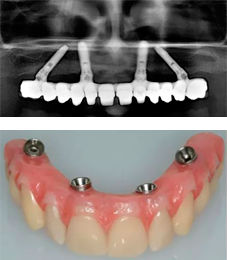

Применяется когда у пациента давно нет зубов и нет возможности установить классические импланты. Данная методика поможет восстановить полную утрату путём инсталляции 4-х имплантатов в переднем отделе верхней или нижней челюсти.